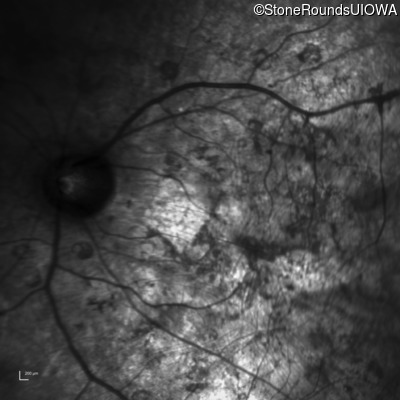

Age at visit: 33 years

OD OS